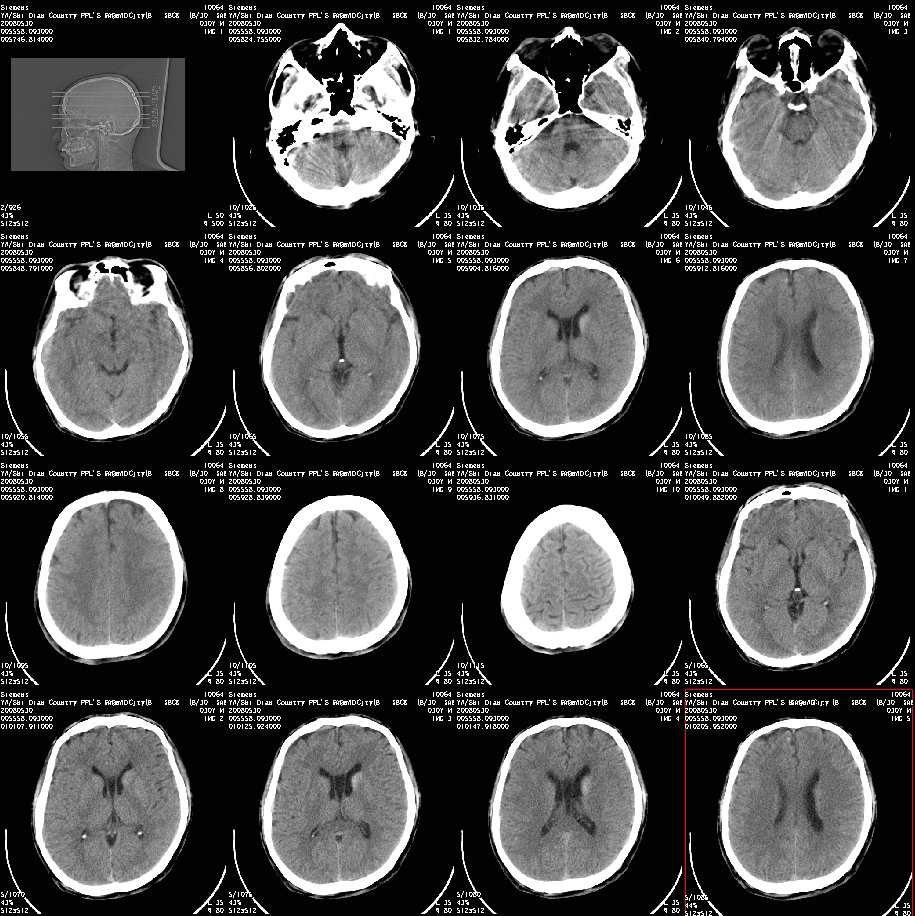

以下是引用随光逐影在2008-7-10 15:19:00的发言:[br]1)考虑左侧尾状核钙化。2)透间隔间腔与vergae腔并存。

以下是引用卜一在2008-7-10 16:43:00的发言:[br]1)考虑左侧尾状核钙化。2)透间隔间腔形成。支持!